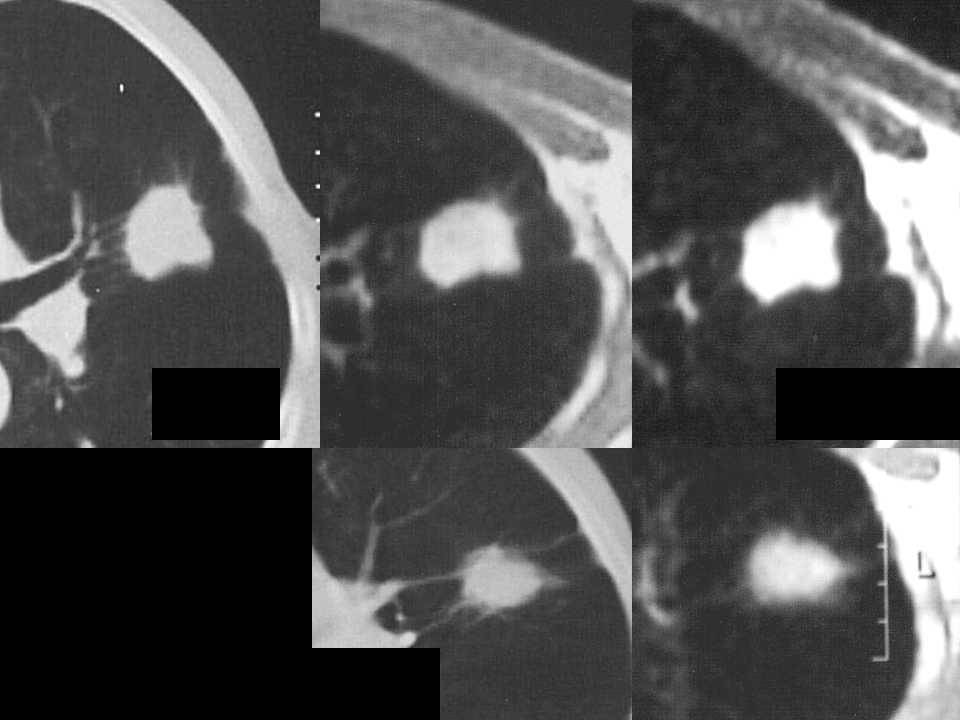

肺癌影像诊断